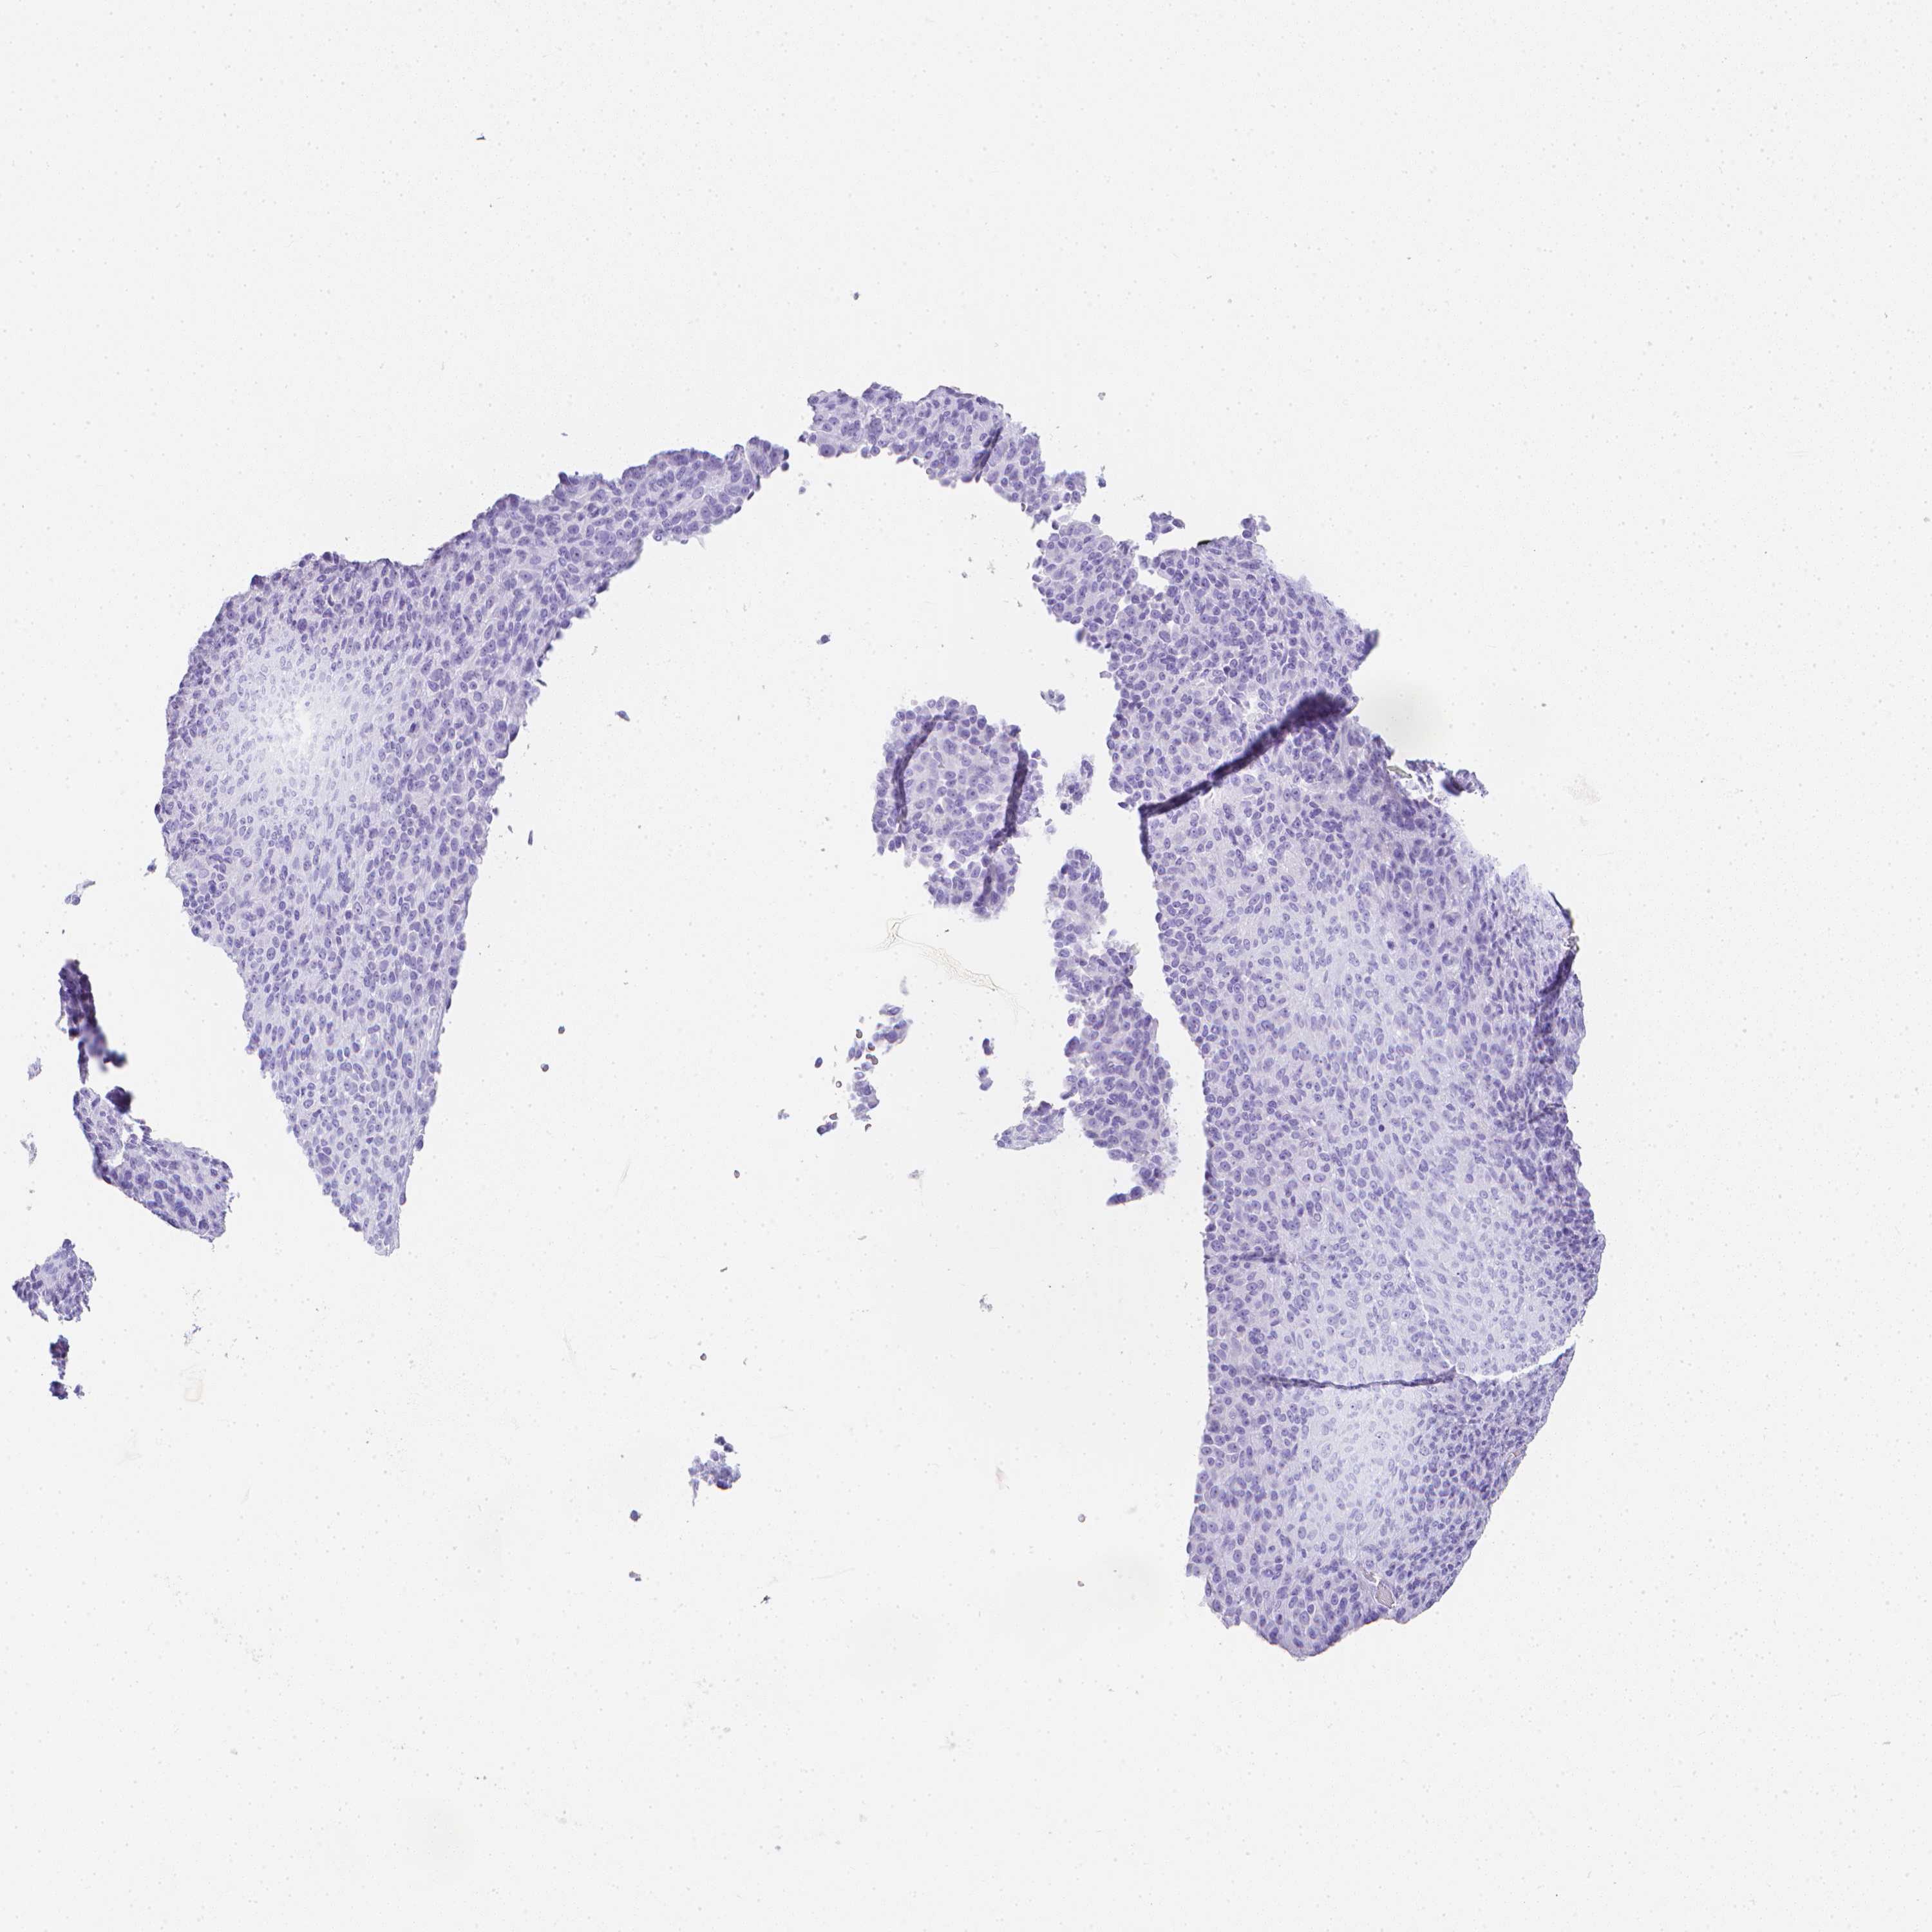

MELANOMA - Protein expressioni

A mouse-over function shows sample information and annotation data. Click on an image to view it in a full screen mode. Samples can be filtered based on level of antibody staining by selecting one or several of the following categories: high, medium, low and not detected. The assay and annotation is described here.

Note that samples used for immunohistochemistry by the Human Protein Atlas do not correspond to samples in the TCGA dataset.

Antibody stainingi

Antibody staining in the annotated cell types in the current human tissue is reported as not detected, low, medium, or high, based on conventional immunohistochemistry profiling in selected tissues. This score is based on the combination of the staining intensity and fraction of stained cells.

Each image is clickable and will lead to virtual microscopy that enables deeper exploration of all samples and also displays staining intensity scores, fraction scores and subcellular localization as well as patient and tissue information for each sample.

Antibody HPA031184

Antibody HPA031185

Antibody HPA031186

Antibody CAB025653

Staining

High

Medium

Low

Not detected

Intensity

Strong

Moderate

Weak

Negative

Quantity

>75%

75%-25%

<25%

None

Location

Nuclear

Cytoplasmic/membranous

Cytoplasmic/membranous,nuclear

Malignant melanoma, NOS

Malignant melanoma, Metastatic site